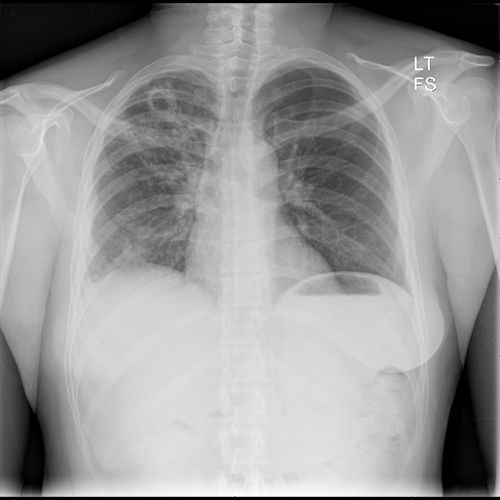

PA Chest X-ray

What best describes the findings on the PA Chest X-ray?

There is a cavitary lesion in the right lung apex with fluffy, nodular airspace opacities. A bronchogenic carcinoma can also present as a cavitating lesion. However, the opacities suggest that this is more likely an infectious process.

View the full study if you'd like to take a look yourself.